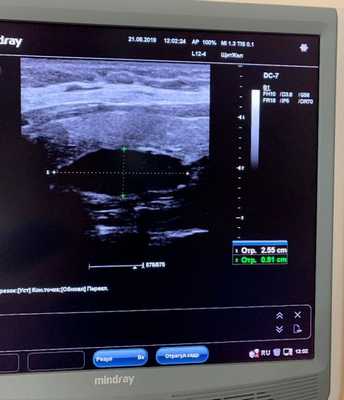

1. Ультразвуковое исследование

Исследуемая область при УЗИ сверху ограничена бифуркацией (разделением) сонной артерии, снизу — грудинной вырезкой, сбоку — сонной артерией/внутренней ярёмной веной [7] . Паращитовидные железы нормального размера обычно не визуализируются с помощью ультразвука. Аденомы проявляются в виде овальных анэхогенных (выглядят чёрными) или гипоэхогенных (выглядят тёмно-серыми) образований, расположенных кзади от щитовидной железы. Обычно можно увидеть эхогенную (светлую) линию, которая отличает щитовидную железу от увеличенной паращитовидной железы. Более крупные аденомы чаще имеют кистозные изменения.

• УЗИ: гипоэхогенное образование с четкими контурами

4. УЗИ при аденоме паращитовидной железы в висцеральном пространстве:

• Серошкальное УЗИ:

о Однородное солидное гипоэхогенное образование с четкими контурами

о Обычно прилежит к щитовидной железе, медиальнее от общей сонной артерии

• Цветовая допплерография:

о Чаще всего гиперваскулярное